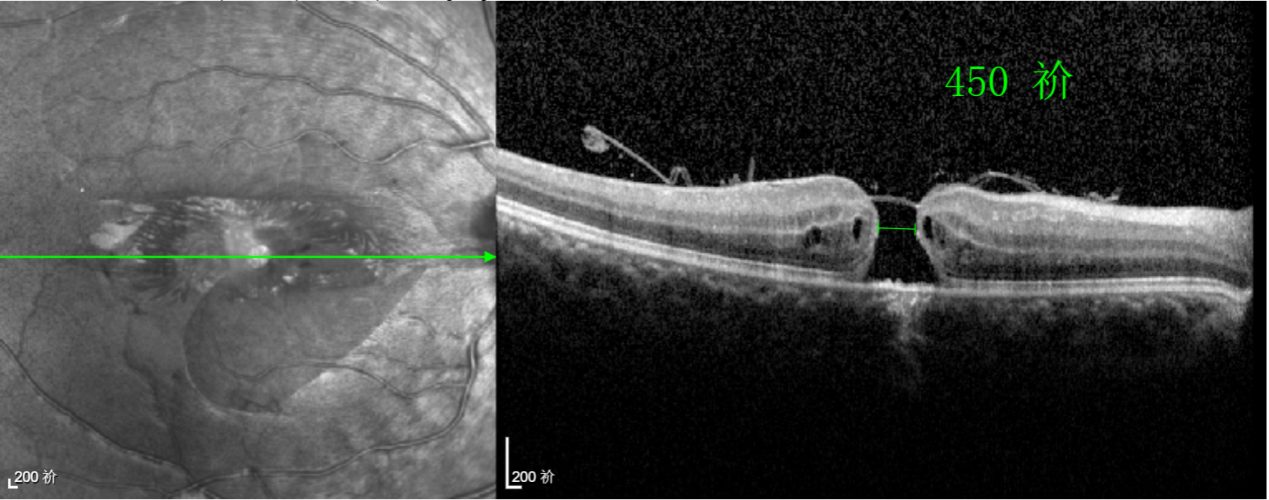

經(jīng)過詳細(xì)的檢查和評(píng)估,王曉波主任決定采用“內(nèi)界膜翻轉(zhuǎn)覆蓋聯(lián)合粘彈劑固定術(shù)”為誠誠進(jìn)行治療。

術(shù)中,醫(yī)生精細(xì)剝離黃斑區(qū)的內(nèi)界膜后,并非直接丟棄,而是巧妙地給它翻個(gè)面,讓它變成一塊天然“創(chuàng)可貼”,嚴(yán)密覆蓋在黃斑裂孔的表面。覆蓋的內(nèi)界膜像微型支架一樣撐住裂孔邊緣,防止它擴(kuò)大;同時(shí),這層膜本身含有能促進(jìn)生長(zhǎng)的“養(yǎng)分”,能顯著刺激裂孔周圍的視網(wǎng)膜組織像爬山虎一樣快速生長(zhǎng)、蔓延過來,最終把裂孔“補(bǔ)”好。

除此之外,利用自體組織覆蓋為黃斑裂孔提供了理想的愈合環(huán)境,裂孔閉合速度顯著快于傳統(tǒng)方法。誠誠接受手術(shù)24小時(shí)后,檢查可見內(nèi)界膜瓣位置良好;術(shù)后1個(gè)月,黃斑裂孔已經(jīng)閉合,視力恢復(fù)到0.5;術(shù)后兩個(gè)月,視力進(jìn)一步提升到0.7。